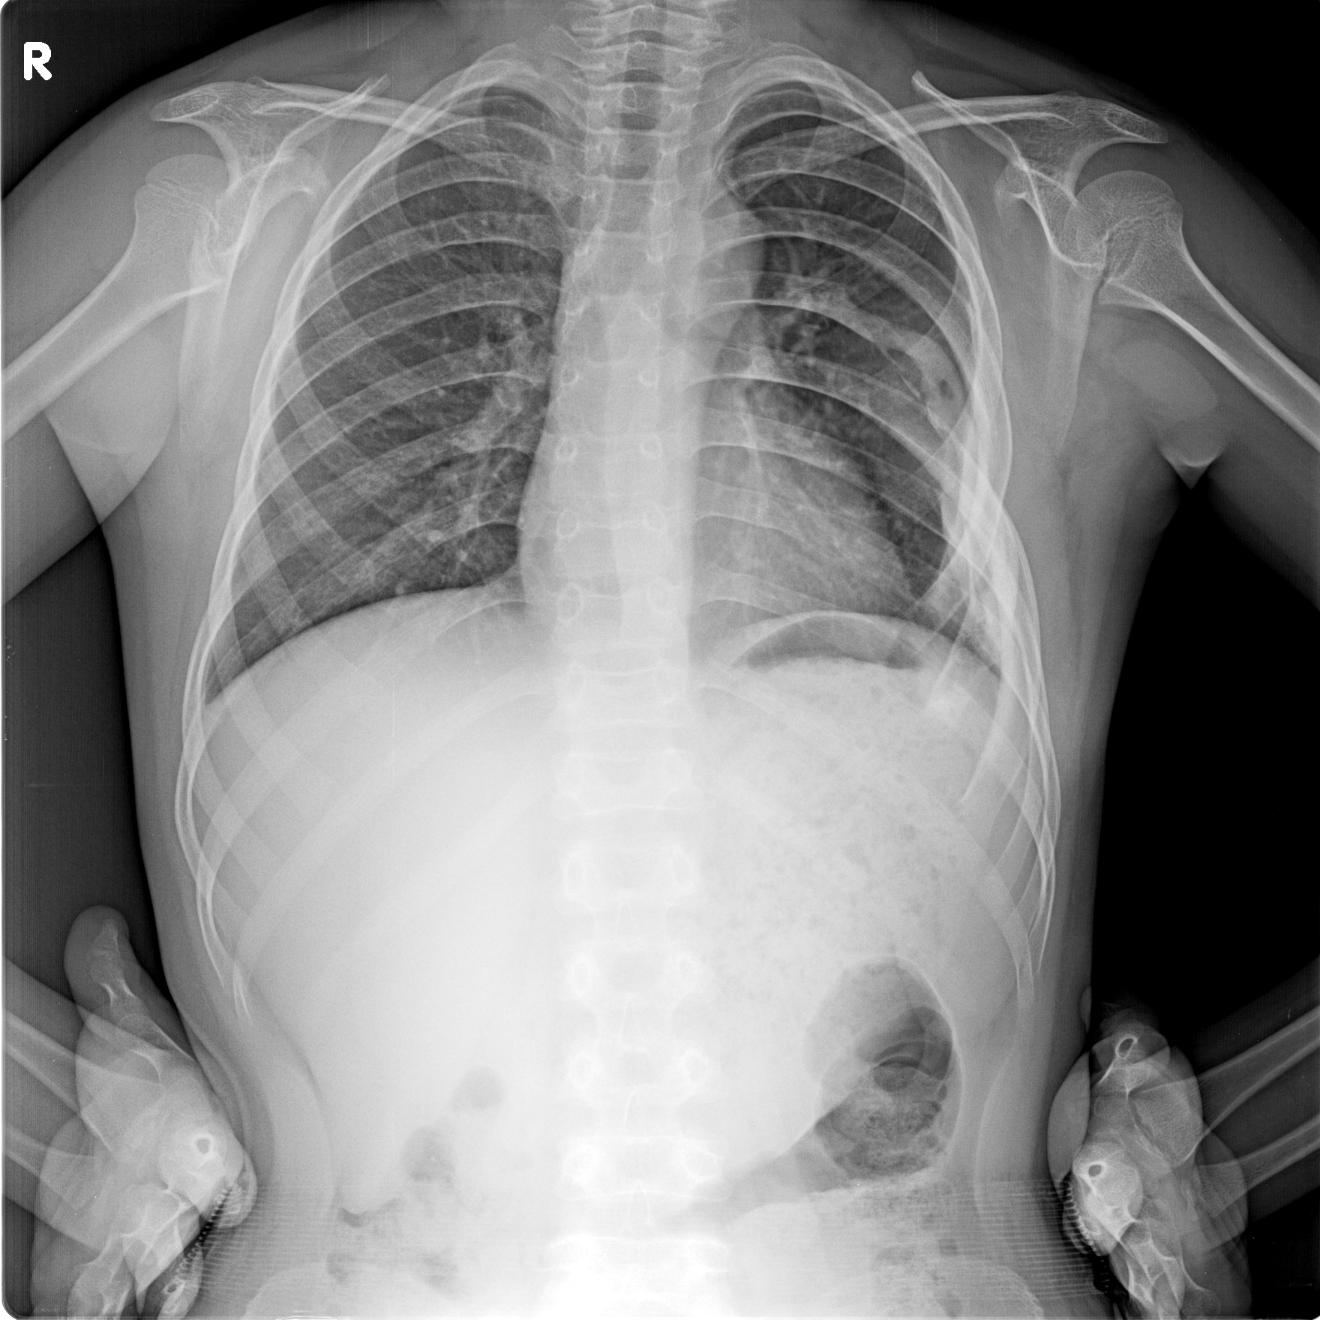

标题: PED0927:男 10y 胸廓隆起 近10天感觉有点疼 [打印本页]

标题: PED0927:男 10y 胸廓隆起 近10天感觉有点疼

追问无其他病史

考虑左侧第6肋肋腋骨质呈膨胀性破坏.后缘骨皮质破坏,髓腔变窄.左外胸壁软组织肿胀.考虑结核可能性大.骨肿瘤不除.